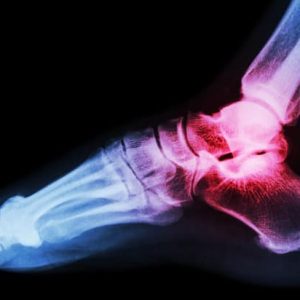

Понякога лигаментите могат да бъдат пренатягани или дори разкъсани (както при изкълчен глезен). Лигаментът може след това да не контролира адекватно ставата – това води до „нестабилност“, която може да постави ненормални натоварвания върху ставите и дисковете в гръбначния стълб. Нестабилността се усложнява от срив в стабилизиращата мускулна система чрез мускулна слабост, умора и лоша координация.